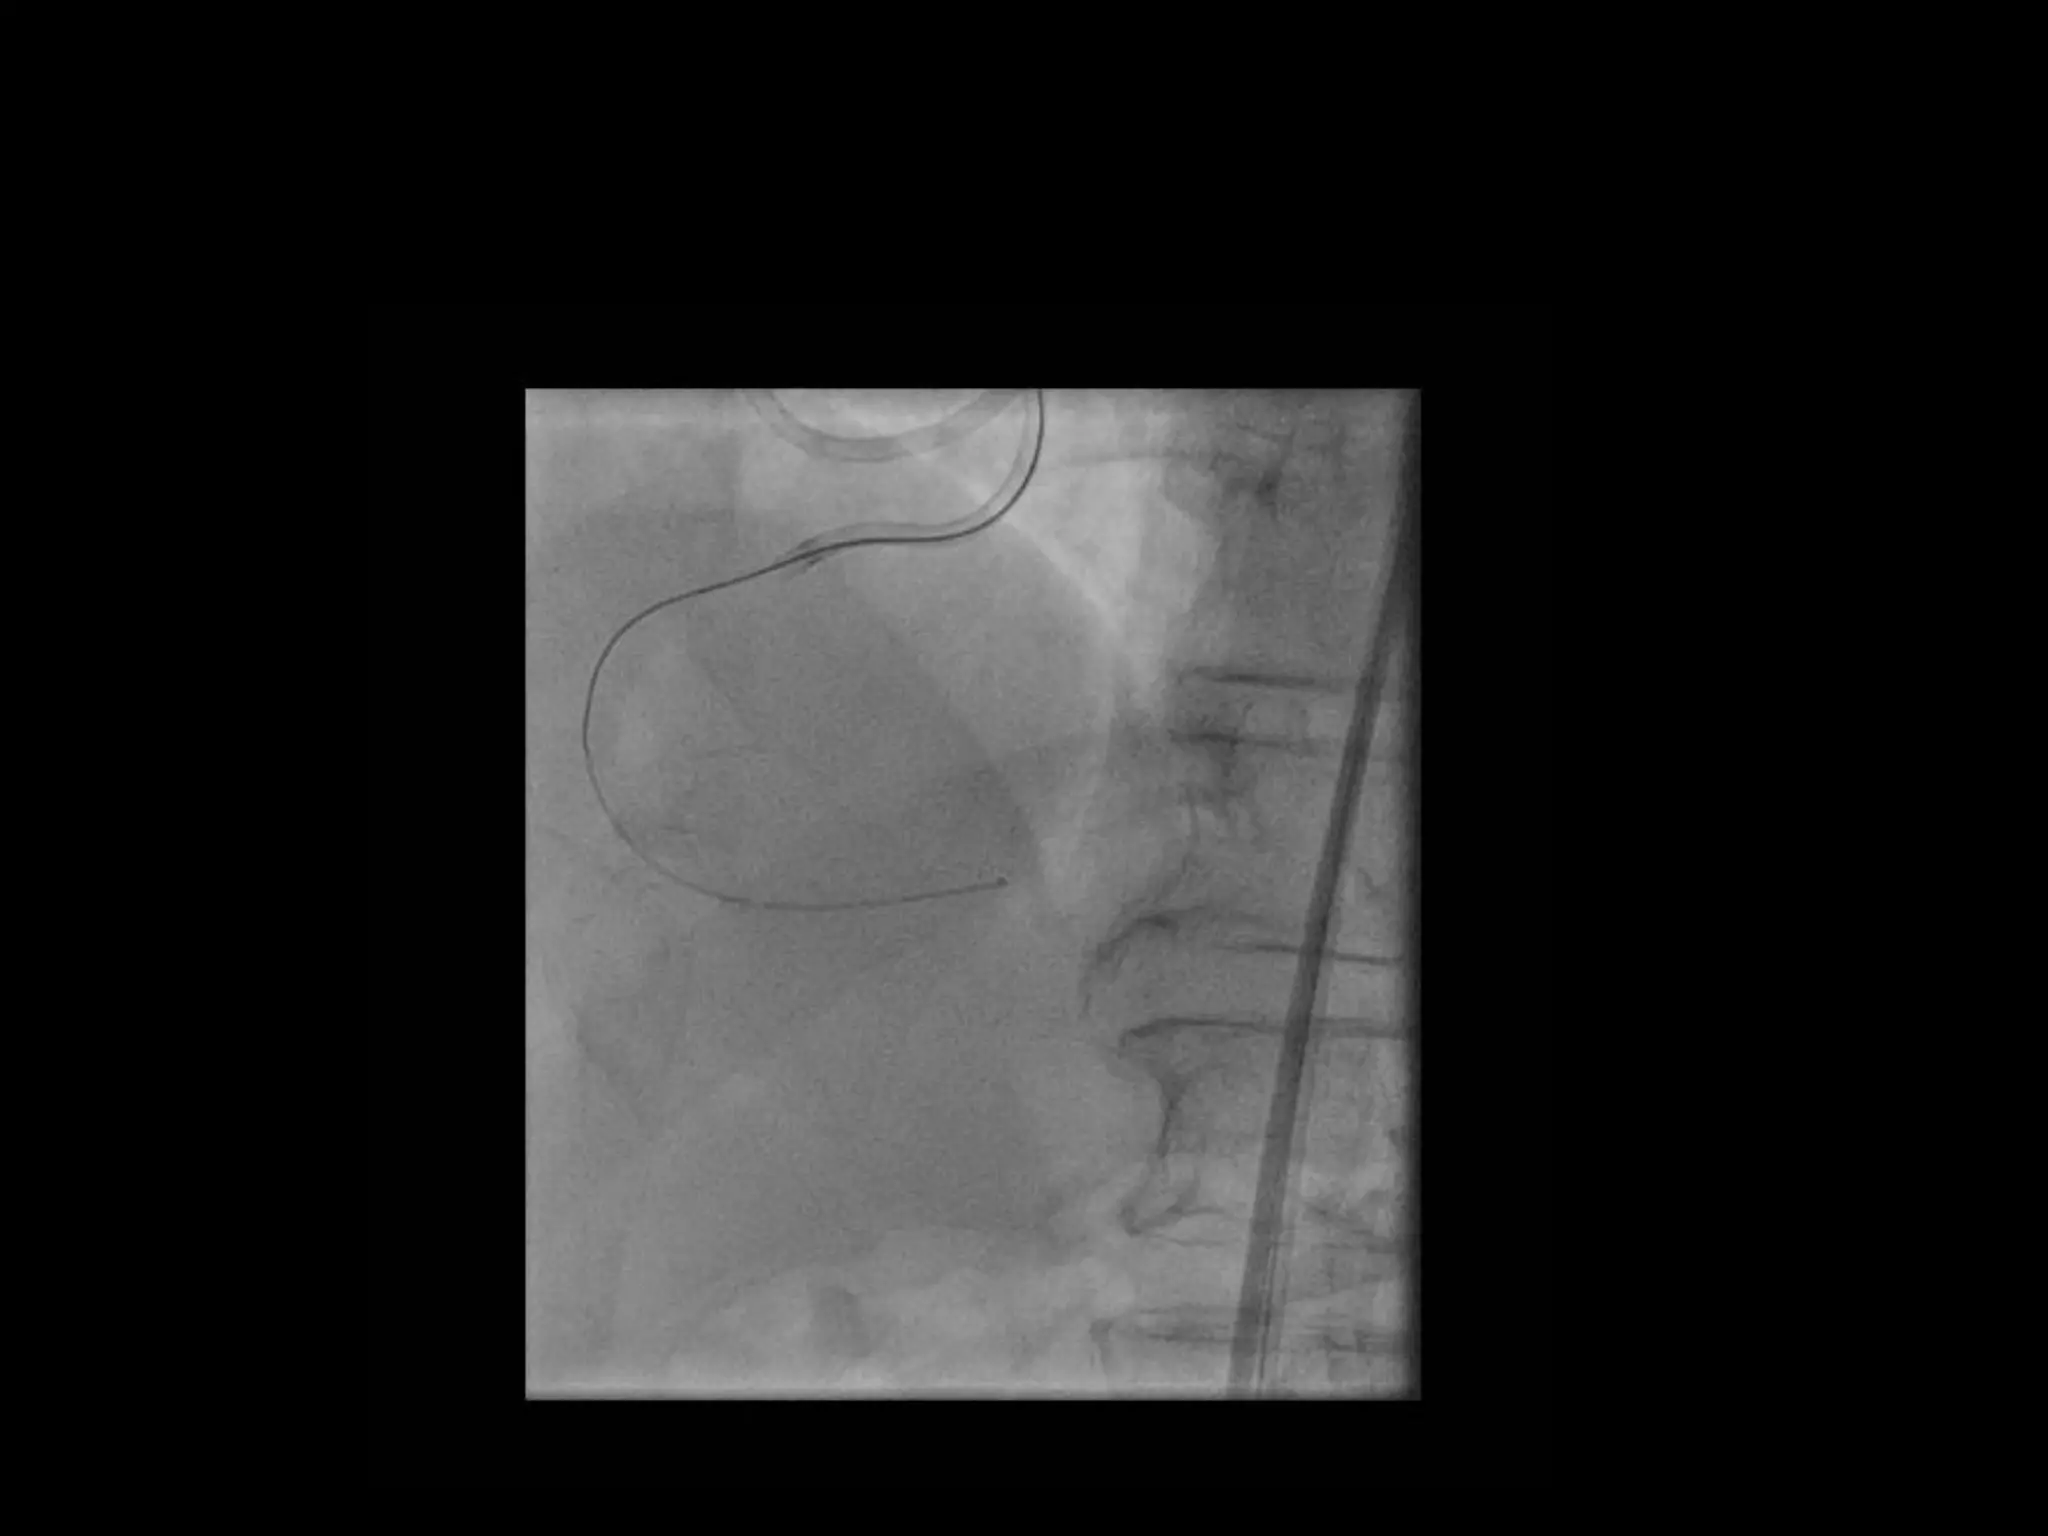

This document provides guidance on evaluating the feasibility of percutaneous coronary intervention (PCI) for a chronic total occlusion (CTO). Key factors to consider include: the patient's tolerance for a long procedure, contrast load, and radiation exposure; the CTO's proximal cap ambiguity, length, distal landing zone, and presence of interventional collaterals; and ensuring good quality angiography. With adequate planning and use of appropriate CTO techniques, feasibility is nearly always present for symptomatic patients. Success rates of CTO-PCI are reported to be 94% when using a planned approach.